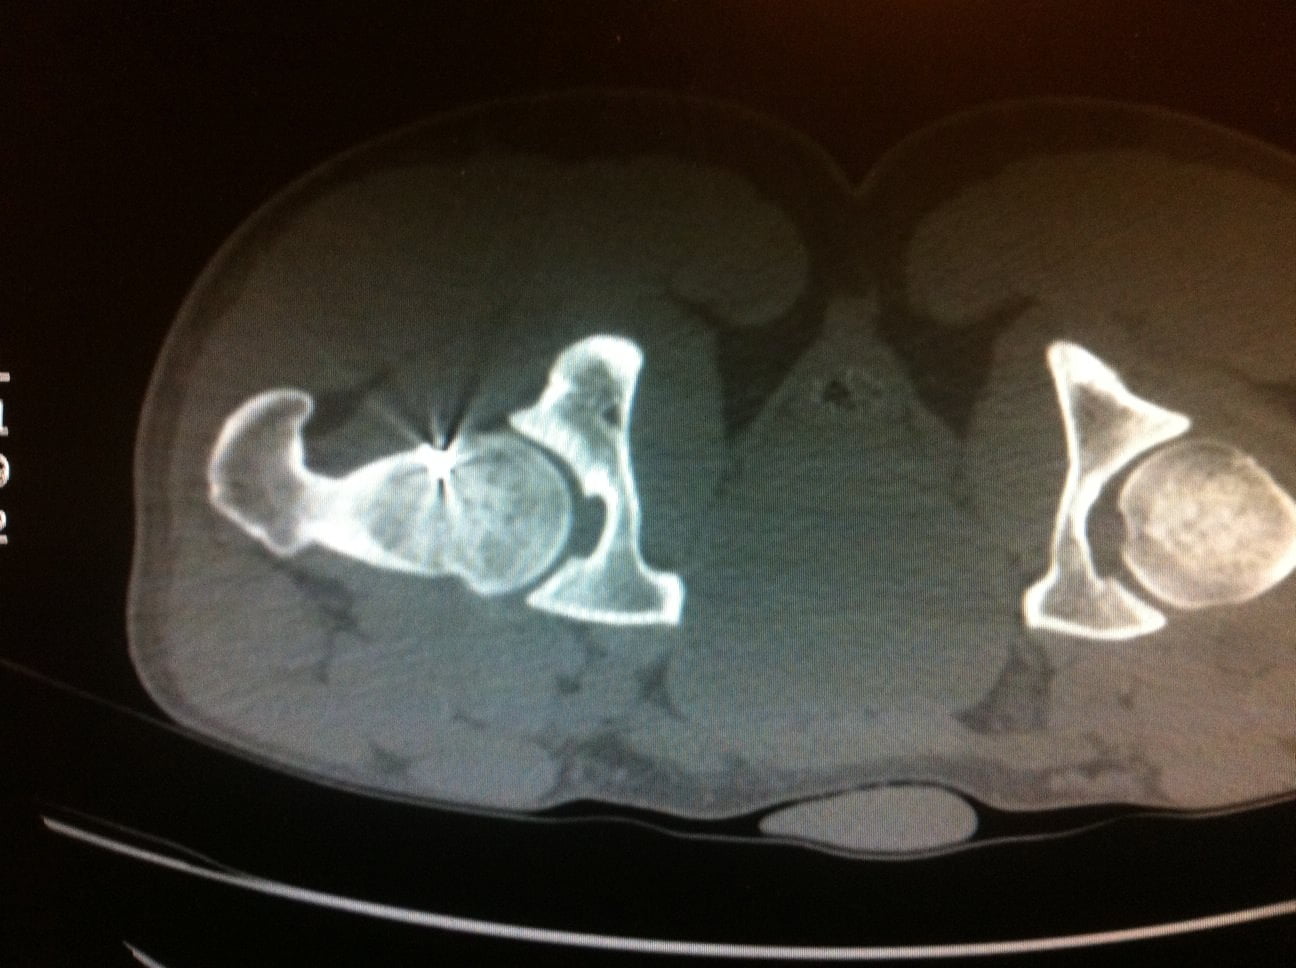

L’Examen est centré sur la région d’intérêt par Acquisition hélicoïdale de Coupes de 1 à 2mm jointives

Le scanner permet de repérer :

Le Nidus = hypodensité à contours nets associé à une hyperdensité calcique linéaire centro-tumorale correspondant à la vascularisation centrale. Une zone hypodense osseuse linéaire au niveau perilésionnel en regard de la condensation est assez spécifique. L’Ostéocondensation périphérique est homogène et peut provoquer une réaction périoste.